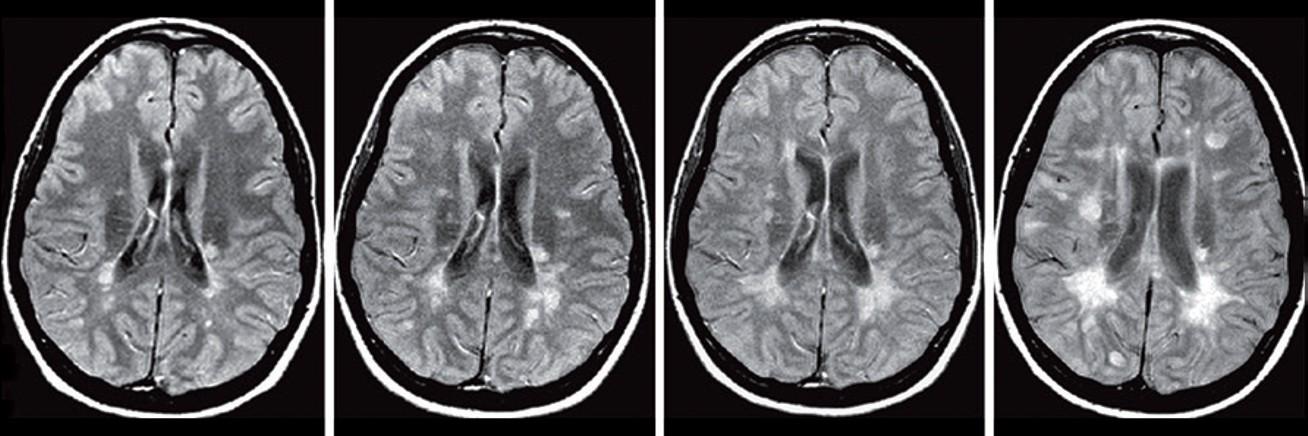

Conventional MRI biomarkers for MS progression

- Slowly Expanding Lesions (SEL’s)

Serial MRI in a patient with relapsing–remitting multiple sclerosis. Proton-density weighted MRI scans obtained at a | baseline, and b | 1 year, c | 2 years and d | 3 years later. Disease progression can clearly be seen in the form of new and enlarging focal lesions over time, shown here as hyperintensities (white spots).

aT2-LV reflects neurodegeneration and has demonstrated sensitivity to MS progression1,2

1. Zivadinov R, et al. Am J Neuroradiol 2019;40:446–452; 2. Dwyer MG, et al. J Neuroimaging 2018;28:490–495; 3. Genovese AV, et al. Radiology 2019;293:424–33.